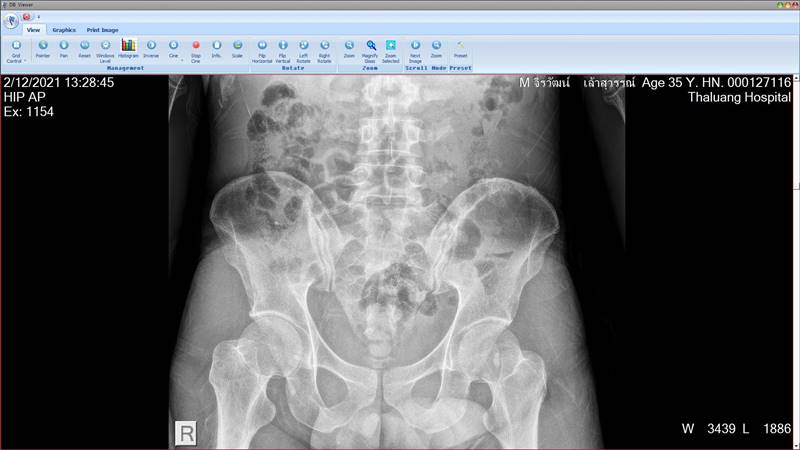

ล่าสุด (21 ธันวาคม 2564) ทนายเกิดผล แก้วเกิด โพสต์รูปและข้อความผ่านเฟซบุ๊ก เผยผลการเอกซเรย์ร่างกายของน้องฟ้าบางส่วน ซึ่งพบว่ามีร่องรอยกระดูกแตกหลายจุด โดยทนายชี้ว่า น้องฟ้าถูกเจ๊กั้ง นายอ้วน รวมถึงสามีของเจ๊กั้ง ร่วมกันทำร้ายร่างกายจนกระดูกแตกแต่ไม่ได้รับการรักษา ทำให้น้องฟ้าต้องทนทุกข์ทรมาน ปล่อยให้บาดแผลหายเองตามธรรมชาติ ซึ่งการที่ไม่ได้รับการรักษาและต่อกระดูกอย่างถูกต้อง ปล่อยให้กระดูกเชื่อมต่อเองตามธรรมชาตินั้น ทำให้การเชื่อมต่อของกระดูกผิดพลาด และร่างกายผิดรูป

"น้องฟ้าถูกทำร้ายจนกระดูกแตกหักทั่วร่างกาย ซ้ำ ๆ กัน หลาย ๆ ครั้ง ตั้งแต่หัวจรดปลายเท้า โดยไม่ได้รับการรักษาอย่างถูกต้อง คิดดูซิครับว่าจะทุกข์ทรมานแค่ไหน" ทนายเกิดผล ระบุ

ภาพจาก ทนายเกิดผล แก้วเกิด